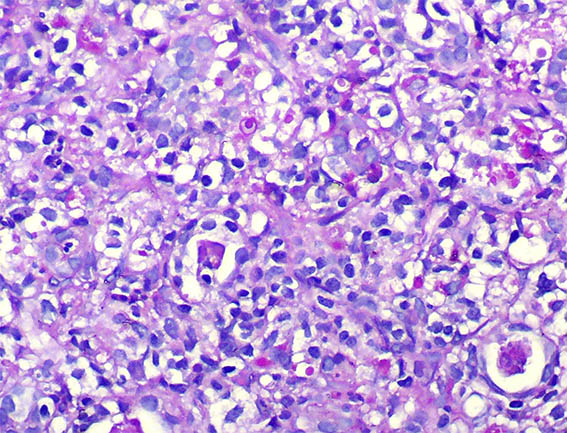

Figure 4. H&E, X400.